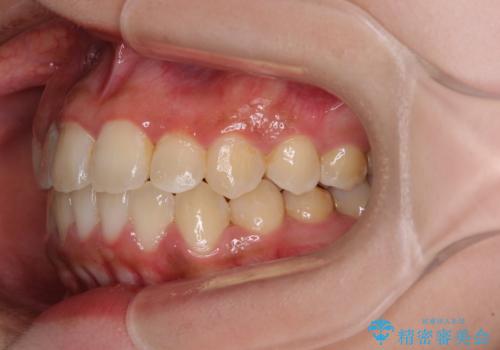

前後に重なった前歯 ワイヤー装置と急速拡大装置を併用したインビザライン矯正

- 前歯の著しい叢生とクロスバイトを気にして来院された患者様です。

叢生が強いため、一見すると抜歯矯正と判断したくなりますが、下顎臼歯が舌側に倒れていることから、上顎骨を側方拡大し、非抜歯矯正の可能性を検討することとしました。

非抜歯矯正が可能となった場合には、インビザラインにて矯正治療を行うこととしました。

急速拡大装置による上顎骨の側方拡大が思った以上にうまくいき、非抜歯での矯正が可能となりました。

内側に倒れていた下顎の臼歯は起き上がり、清掃性も大幅に改善されました。